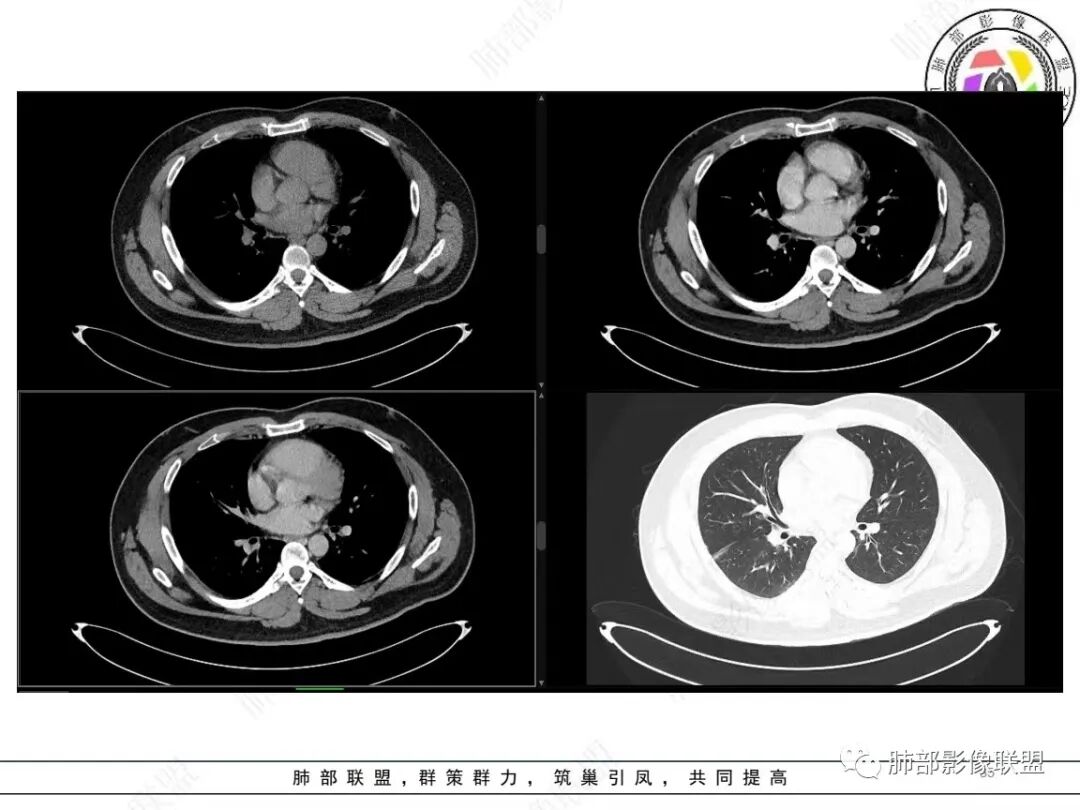

中年人,咳血,左肺上叶实性团块,边界清晰,与胸膜分界不清,可见栽赃表现,病灶推挤支气管及肺血管内移,增强可能条纹血管影,总体强化明显,考虑恶性或交界性肿瘤,间叶组织来源,肉瘤,SFT,肉瘤样癌,滑膜肉瘤。

左肺上叶胸膜肿块,浅分叶,边缘光整,密度不均匀,周围气管及血管受压推移,边缘强化,考虑肉瘤,鉴别SFT

左上肺软组织肿块,周围散在磨玻璃影,界不清,窄基底贴于胸壁,胸膜下脂肪间隙不清,呈低强化,胸膜下见。与主病灶强化方式一样的病变,2R区见肿大淋巴。考虑恶性,间叶组织来源合并出血。

青年男性,咯血;CT示左肺上叶胸膜下软组织肿块,边界尚清,宽基底与胸膜相连,增强动脉期内见细条状血管影,轻度延迟强化,定位:肺外,胸膜外脂肪存在,考虑脏层胸膜起源;定性:考虑SFT。

有血供,强化不明显,周围肺出血,肺组织受压改变,定位肺外,胸膜增厚,部分胸膜下脂肪间隙存在,不确定肋骨是否受侵犯,部分层面与肺动脉分界不清,感觉推移,如果供血要考虑sft,强化不符合,有血管进入,但是强化不明显,密度相对均匀,所以不考虑坏死,富含粘液可能,咯血,说明累及支气管了,有一定侵袭性,肿块大,考虑间叶来源肿瘤,与胸膜接触面相对不是宽基底,综合考虑滑膜肉瘤可能,典型的滑膜肉瘤一般铺路石改变,这个又觉得信号相对均匀了一些学习中